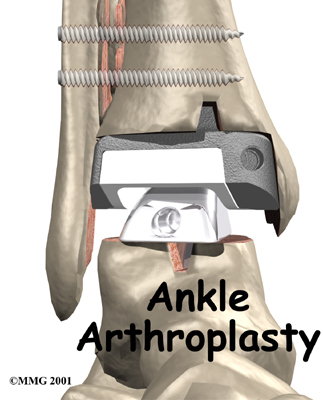

Surgery to replace the ankle joint with an artificial joint (called ankle arthroplasty) is becoming more common. This surgery is not done as often as replacement of the knee or hip joints. Still, when necessary, this operation can reduce the pain from arthritis of the ankle. Recent advances in the design of the artificial ankle and changes in the way the operation is performed have made artificial ankle replacement a growing alternative to ankle fusion for the treatment of ankle arthritis.

The artificial ankle

Each artificial ankle prosthesis is made of two parts:

- The tibial component is the part of the artificial joint that replaces the socket portion of the ankle (the top section).

- The talus component replaces the top of the talus.

The tibial component is usually made up of two parts: a flat metal piece called a metal tray that is attached directly to the tibia bone, and a plastic cup that fits onto the metal piece, forming a socket for the artificial ankle joint. The talus component is made of metal and fits into the socket of the tibial component.